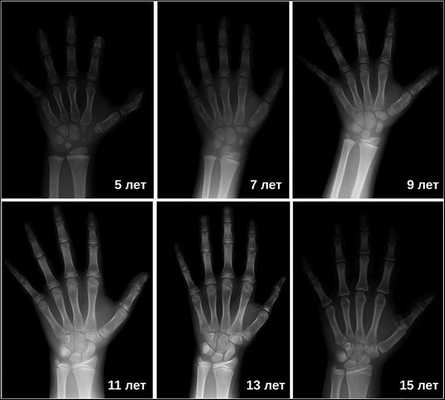

Диагностику начинают с опроса и оценки роста родителей пациента. Проводят антропометрические измерения (роста, веса и т.д.) и оценивают половое развитие. Определяют костный возраст ребенка, используя рентгенографию.

Рентгенография турецкого седла выявляет его детскую форму («стоячий овал») и широкую (т. н. ювенильную) спинку. При увеличении размеров турецкого седла и наличии участков обызвествления, в первую очередь, следует думать об опухоли. Рентгенография лучезапястных суставов и кистей позволяет определить рентгенологический («костный») возраст. При гипофизарном нанизме отмечается значительное замедление процессов окостенения скелета.

Затем врачи определяют костный возраст. Сделать это можно с помощью рентгена или УЗИ запястья. В норме костный возраст может отставать или опережать паспортный на два года.